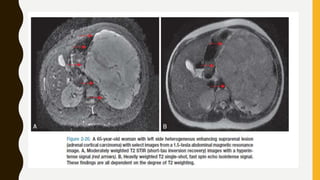

Adrenal Cortical Carcinoma

• An adrenal cortical carcinoma (ACC) diagnosis is usually made using a combination of

clinical factors and imaging characteristics (Fig. 2-20).

• T2- and T1-weighted images with Gd usually are heterogeneous with a high SI and a

heterogeneous enhancement, respectively.

• CSI exhibits a low signal.